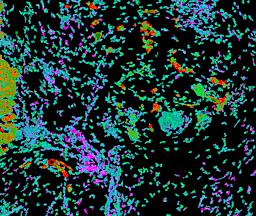

Pancreatic ductal adenocarcinoma is a lethal disease with limited treatment options and poor survival. We studied 83 spatial samples from 31 patients (11 treatment-naïve and 20 treated) using single-cell/nucleus RNA sequencing, bulk-proteogenomics, spatial transcriptomics and cellular imaging. Subpopulations of tumor cells exhibited signatures of proliferation, KRAS signaling, cell stress and epithelial-to-mesenchymal transition. Mapping mutations and copy number events distinguished tumor populations from normal and transitional cells, including acinar-to-ductal metaplasia and pancreatic intraepithelial neoplasia. Pathology-assisted deconvolution of spatial transcriptomic data identified tumor and transitional subpopulations with distinct histological features. We showed coordinated expression of TIGIT in exhausted and regulatory T cells and Nectin in tumor cells. Chemo-resistant samples contain a threefold enrichment of inflammatory cancer-associated fibroblasts that upregulate metallothioneins. Our study reveals a deeper understanding of the intricate substructure of pancreatic ductal adenocarcinoma tumors that could help improve therapy for patients with this disease.